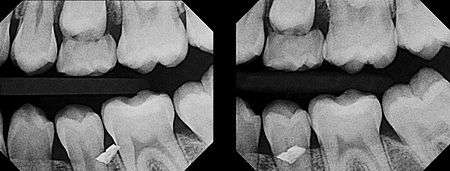

In 1909, Clark described a radiographic procedure for localizing impacted teeth to determining their relative antero-posterior position.[1] If the two teeth (or, by extension, any two objects, such as a tooth and a foreign object) are located in front of one another relative to the x-ray beam, they will appear superimposed on one another on a dental radiograph, but it will be impossible to know which one is in front of the other. To determine which is in front and which is behind, Clark proposed his SLOB rule, as a complicated set of three radiographs, but which can be simplified as follows using just two:

- Expose another film while angle of the x-ray beam has been changed. If an object moves in the same direction as the source of the x-ray beam, it is lingual to the other object. If the object moves in the opposite direction of the source, it is buccal to the other object.

- Same Lingual; Opposite Buccal

In 1952, Richards amended this rule using only 2 radiographs,[2][3] asserting that the object positioned more buccally will move more relative to the object positioned more palatally or lingually.

As a generalization, but not specifically stated as part of Richards' buccal object rule, the more buccal an object is (i.e. the closer it is to the x-ray source) the more it will move in the second radiograph when repositioning the x-ray source.